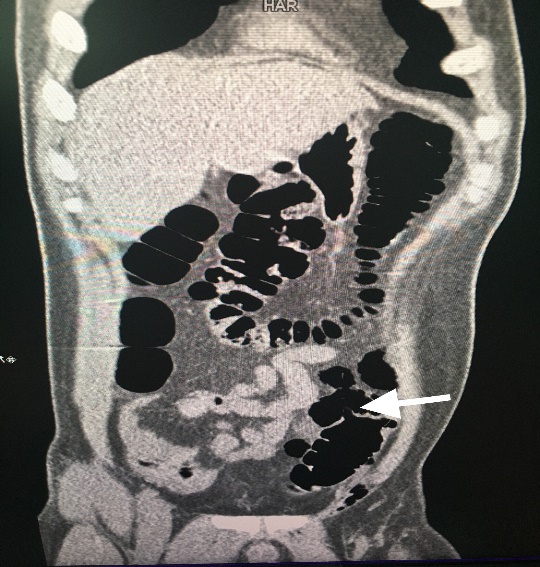

Bệnh nhân được theo dõi thêm tình trạng bụng. Sau 1 giờ 15 phút khám lại thấy tình trạng đau bụng của bệnh nhân vẫn liên tục, không giảm nhưng cũng không lan rộng ra các vùng khác, đau cũng chỉ giới hạn 1 vùng như lần thăm khám trước. Do nghi ngờ có vỡ tạng rỗng nên bệnh nhân được chỉ định chụp CT scanner để tìm dấu hiệu hơi tự do ổ phúc mạc. Kết quả phim CT scanner không phát hiện hơi tự do ổ phúc mạc, tuy nhiên có hình ảnh thâm nhiễm viêm kèm bóng hơi cạnh đại tràng sigma, ít dịch vùng hạ vị (Hình 2).

Hình 2. thâm nhiễm viêm kèm bóng hơi cạnh

đại tràng sigma

Với hình ảnh này chúng tôi nghĩ đến 2 khả năng: viêm túi thừa đại tràng xích ma hoặc vỡ đại tràng xích ma dưới thanh mạc. Tuy nhiên đau khởi phát sau một chấn thương bụng kín nên khả năng vỡ đại tràng dưới thanh mạc được ưu tiên và tìm cách để xác minh. Bênh nhân được đặt thông hậu môn và bơm khoảng 500 ml khí sau đó kẹp thông và chụp lại phim CT scanner. Kết quả phim CT scanner lần này bóng hơi cạnh đại tràng sigma trên phim trước to ra kèm có hơi tự do ổ phúc mạc (Hình 3 và 4). Chẩn đoán vỡ đại tràng sigma được xác định và bệnh nhân được mổ cấp cứu. Trong mổ phát hiện đai tràng sigma vỡ dưới thanh mạc ở bờ tự do, kích thước khoảng 1 cm, bờ lỗ vỡ bình thường, không có dấu hiệu của túi thừa đại tràng. ổ bụng sạch, có ít dịch xuất tiết (Hình 5). Lỗ vỡ được đóng ngay thì đầu bằng vicril 2.0 hai lớp khâu vắt. Quá trình hậu phẫu bình thường, bệnh nhân được xuất viện sau 7 ngày, không có biến chứng sau mổ .